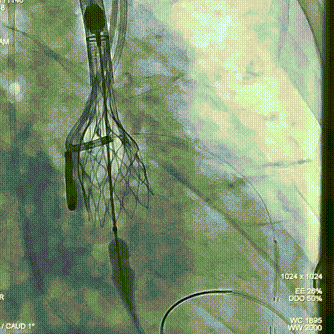

球囊预扩

瓣膜初始定位

即刻超声评估示瓣周漏显著降低